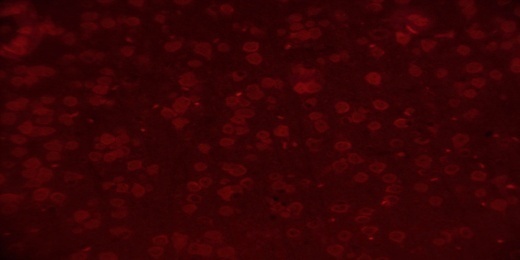

Immunoflourescence

5 µM-thick paraffin sections through matched coronal levels of the SNpc and ST were processed as described above and non-specific binding was blocked by 1 h incubation in 1.5% BSA. Sections were incubated with primary antibody, mouse anti-NeuN (1:100) for one hour and then subsequently incubated with secondary antibody, TRITC conjugated goat anti-mouse IgG (1:20) for half an hour at room temperature. The number of positive cells in SNpc and ST was counted under x400 magnification with image analysis software (Motic DMB1–2MP, China). Percentage immunopositive cells were calculated as: (Number of immunopositive cells/mm2)/(Total number of cells/mm2) X 100.

TEL increased NeuN expressions in MPTP intoxicated mice brain

SNpc and ST regions of MPTP mice brain showed a significant decrease in % NeuN immunopositive cells [F (4,10) = 274.1, p<0.01 and F (4,10) = 86.24, p<0.01, respectively] when compared to the vehicle treated mice. TEL (3 and 10 mg/kg) significantly (p<0.01) increased % NeuN immunopositive cells in both the regions in comparison to MPTP mice (fig. 4).

Fig. 4: Effect of TEL on % NeuN immunopositive cells in MPTP intoxicated mice brain. Pictures represent NeuN immunopositive cells of (A) SNPc and (B) ST brain regions X 400 magnification. (1) Normal control, (2) MPTP induced mice brain, (3) TEL (3 mg/kg b. wt.) administered MPTP mice brain, (4) TEL (10 mg/kg b. wt.) administered MPTP mice brain and (5) TEL (10 mg/kg b. wt.) administered normal mice brain. (C) Values were expressed in mean±SEM, n=4 animals/group, statistical analysis was performed using one way ANOVA followed by Tukey’s multiple comparison test, ## indicates p value<0.01 Vs group I, ** indicates p value<0.01 Vs group II